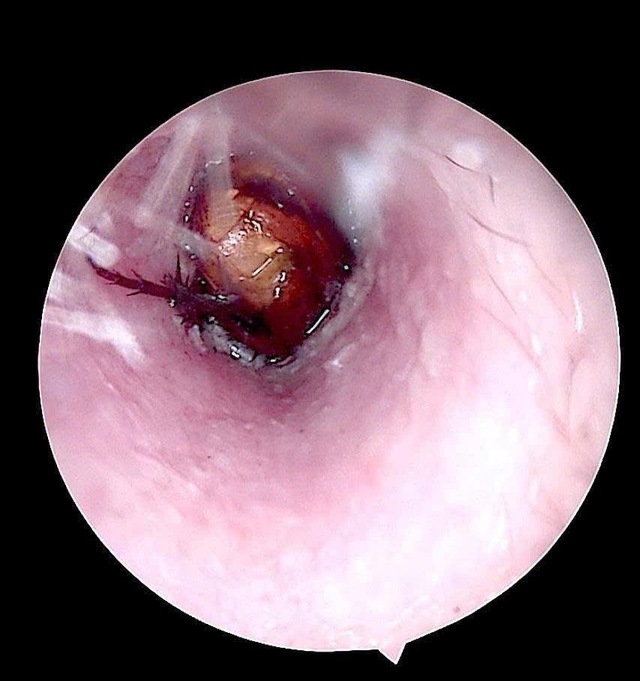

Qua kiểm tra, bác sĩ ghi nhận ống tai ngoài bên phải của bệnh nhân có hiện tượng xung huyết, có dị vật sống. Các bác sĩ đã tiến hành nội soi, gắp dị vật là một con côn trùng có kích thước khoảng 1,5cm.

Dị vật là côn trùng còn sống kích thước khoảng 1,5cm.

Kiểm tra sau lấy dị vật, phát hiện màng nhĩ bệnh nhân nề đỏ do phản ứng viêm và kích thích trong quá trình tự lấy dị vật.